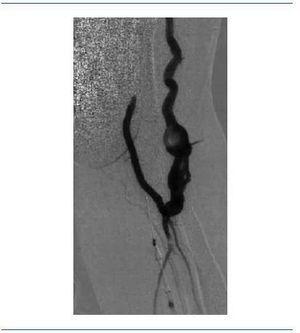

Acude a su sesión de hemodiálisis habitual el 19 de junio de 2007, y a falta de 1,15 h del final (de un total de 4 de diálisis) y habiendo transcurrido toda ella con absoluta normalidad, tras notar una sensación de latido en la FAV, presenta un aumento brusco de la presión arterial y posteriormente de la presión venosa, a pesar de lavados y de una segunda dosis de enoxaparina de 20 mg. Se ausculta la FAV, que no presenta ni soplo ni thrill, con el diagnóstico clínico de trombosis de FAV. Se desconecta a la paciente y se remite al hospital de referencia para intento de trombólisis. A su llegada se realiza analítica, destacando una hemoglobina de 13,1, hematocrito de 38,6% y plaquetas 137.000/mm3. Se realiza asimismo un electrocardiograma (ECG), detectando una arritmia completa por fibrilación auricular, con frecuencia de alrededor de 80 latidos por minuto. En el centro hospitalario proceden al implante de un catéter femoral provisional el 21 de junio de 2007 para poder dializarla, realizando ese mismo día una fistulografía mediante punción de la arteria humeral izquierda; en ella aprecian signos de probable embolismo arterial (figura 1), por lo que se indica el tratamiento con perfusión de 80.000 UI de urocinasa durante 24 horas. En el control posterior se objetiva una repermeabilización de la FAV, con presencia de dilataciones aneurismáticas y trombos en la vena de retorno, así como algún defecto de repleción en la arteria distal (figura 2). El 23 de junio de 2007, ante la resolución del embolismo de la FAV, y tras comprobar su buen funcionamiento al dializarse a través de ésta, se procede a la retirada del catéter femoral.

Figura 2. Fístula recuperada tras tratamiento. Presencia de dilataciones aneurismáticas (y trombosis) en la vena de retorno. Defectos de repleción también en la arteria distal.